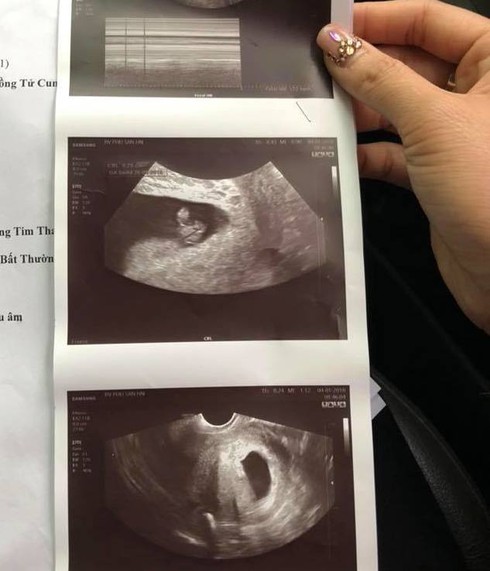

Kết quả siêu âm thai của chị M. |

Khi vào viện, chị M. được bác sĩ chuyển lên khoa sản để khám. Bác sĩ khám cho chị M. là bác sĩ Tiến. Sau khi siêu âm bác sĩ cho biết mới thấy túi ối chưa thấy thai. Bác sĩ cho làm thêm các xét nghiệm máu và chẩn đoán theo dõi sảy thai.

Vì theo kết quả xét nghiệm là thai chắc chắn đã chết lưu. Không có tim thai không có chiều dài đầu mông. Chị M. cho cho biết, nghe câu nói của bác sĩ, bản thân chị đau đớn như rụng rời chân tay vì đã có kết luận cuối cùng từ bác sĩ.

"Sang BV Phụ Sản Hà Nội tôi được đi siêu âm luôn và kết quả là tất cả các chỉ số thai bình thường, bác sĩ cho biết con tôi bình thường không bị làm sao. Bác sĩ cũng cho rằng, đó chỉ là do tôi bị động thai, bác sĩ có nói thêm, thai bé như thế phải siêu âm đầu dò mới chẩn đoán chính xác được. Sau đó, bác sĩ cho tôi đơn thuốc về nhà nghỉ ngơi điều trị tiêm cho thai ổn định”.

Chị M. lại quay lại gặp bác sĩ Tiến và hỏi cho ra vấn đề thì bác sĩ Tiến cho rằng quên không chỉ định siêu âm đầu dò. Chị M. cho biết nếu cứ tin lời bác sĩ ở Bệnh viện Đa khoa Đức Giang chắc chị đã mất con rồi và chị cảm thấy mất niềm tin hoàn toàn vào bác sĩ.